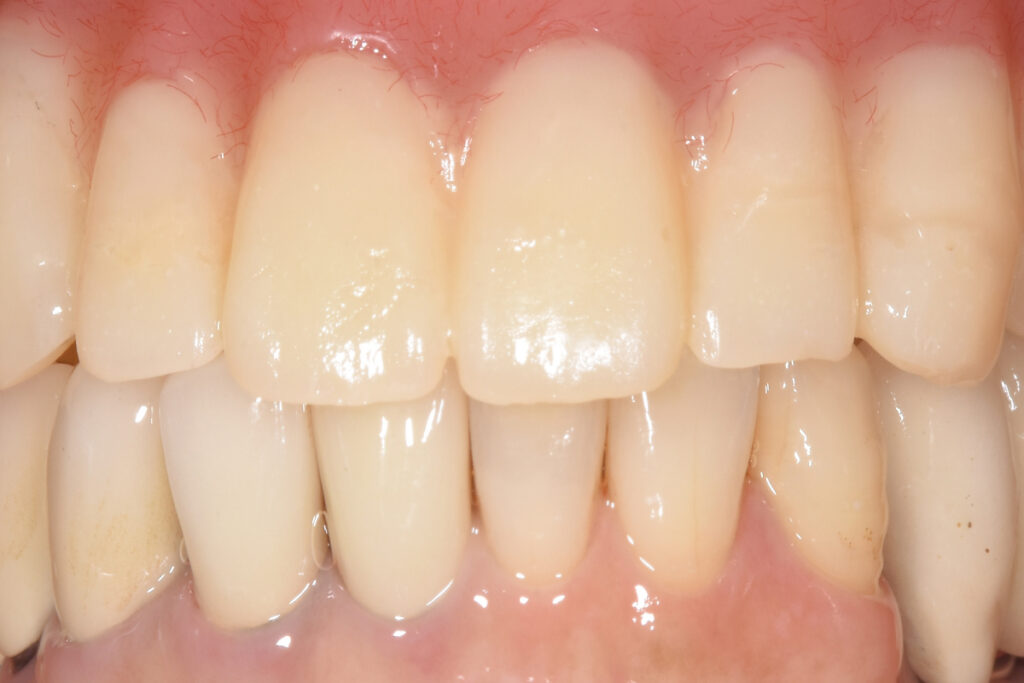

■結果としての状態

治療は完遂しました。現在は定期管理下で、機能的・構造的に安定した状態を維持しています。患者の実感は「噛める」だけではありません。「これ以上悪化させないで済む」という安心が残りました。